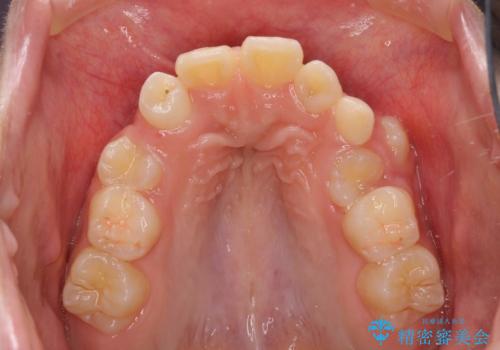

永久歯が生えてこない ワイヤー矯正で複雑な状態を正常咬合へ誘導する

- 乳歯の晩期残存による永久歯の萌出遅延・過剰歯・萌出異常

など多くの問題を抱えていた。

乳歯がうまく抜けず、過剰歯が存在していたことにより、永久歯が位置異常をおこし、非常に複雑な状況となってしまっていました。